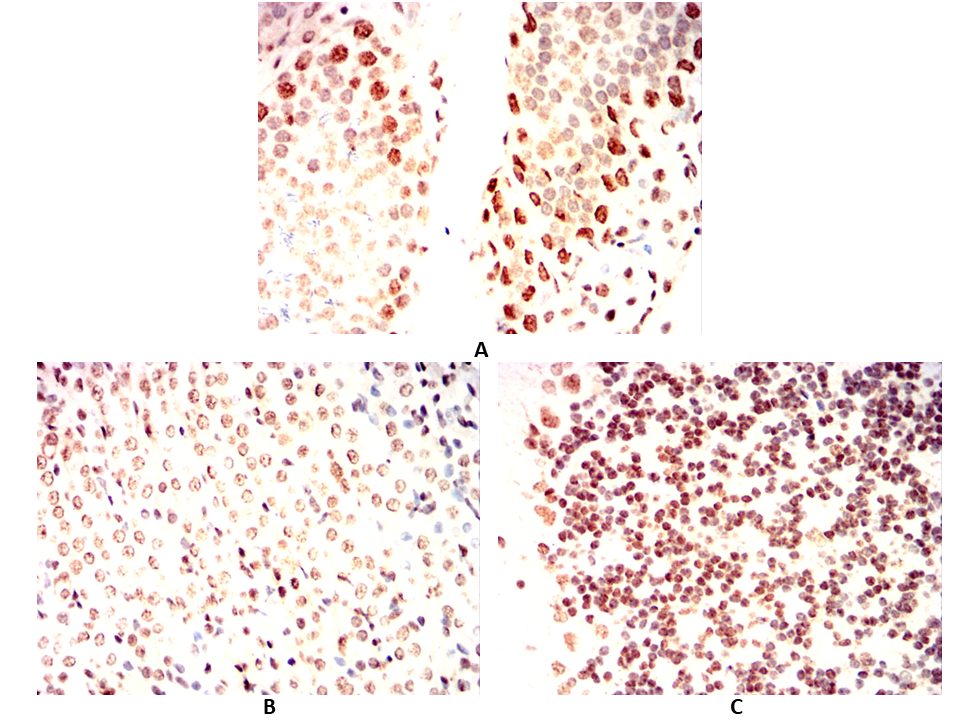

Immunohistochemical analysis of paraffin-embedded Mouse testicles(A)Mouse kidney(B)Mouse cerebellum(C) using EBF1 mouse mAb with DAB staining.